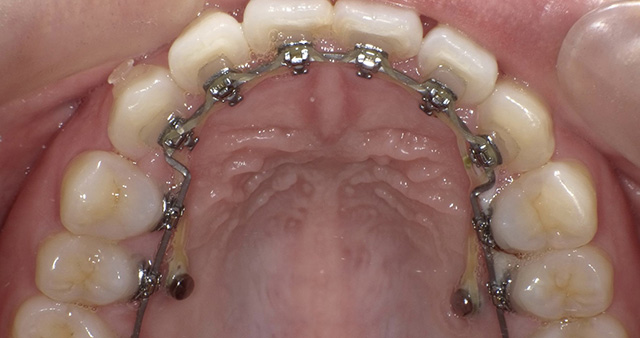

歯の表面にワイヤーとブラケットと呼ばれる固定装置を装着して歯列を整えていく方法で、歯列矯正の中で最も広く行われています。数ミリ単位で歯の移動が可能です。

最近では、歯と同じ色の目立ちにくいブラケットやワイヤーが揃っており、素材を選ぶことで目立ちにくくすることが可能です。